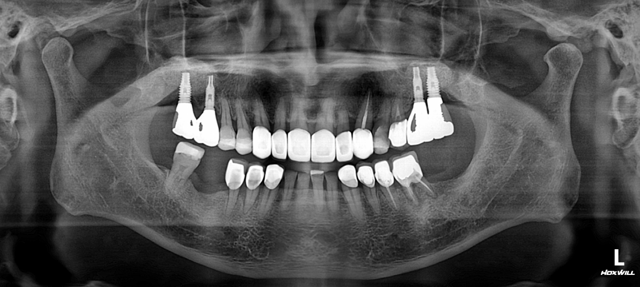

하악 다수치아 임플란트 보철.

양측 어금니를 모두 임플란트 보철로 마무리 한 증례입니다.

이런 케이스에서 보철 완료 후 시간이 조금 지났을 때 어금니가 잘 닿지 않게 되는 경우가 종종 있습니다.

분명히 닿게 해 놨는데도 임플란트 보철 후 저작활동이 활발해 지면서 턱의 위치가 재정립 되고

위치가 변하면서 뒤쪽이 뜨게 되는 것이죠.

임플란트 보철은 시간적인 요소도 같이 고려하며 추적 관찰 해야 합니다.